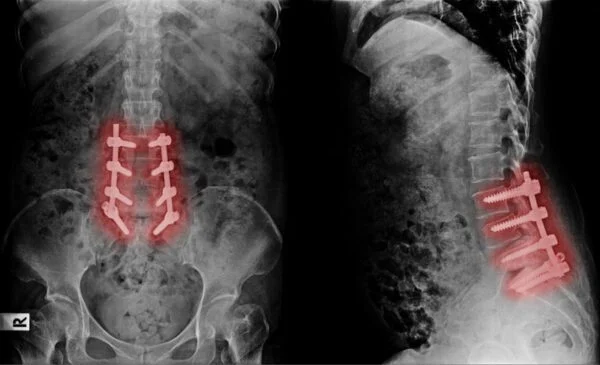

X-ray images of a failed back surgery procedure